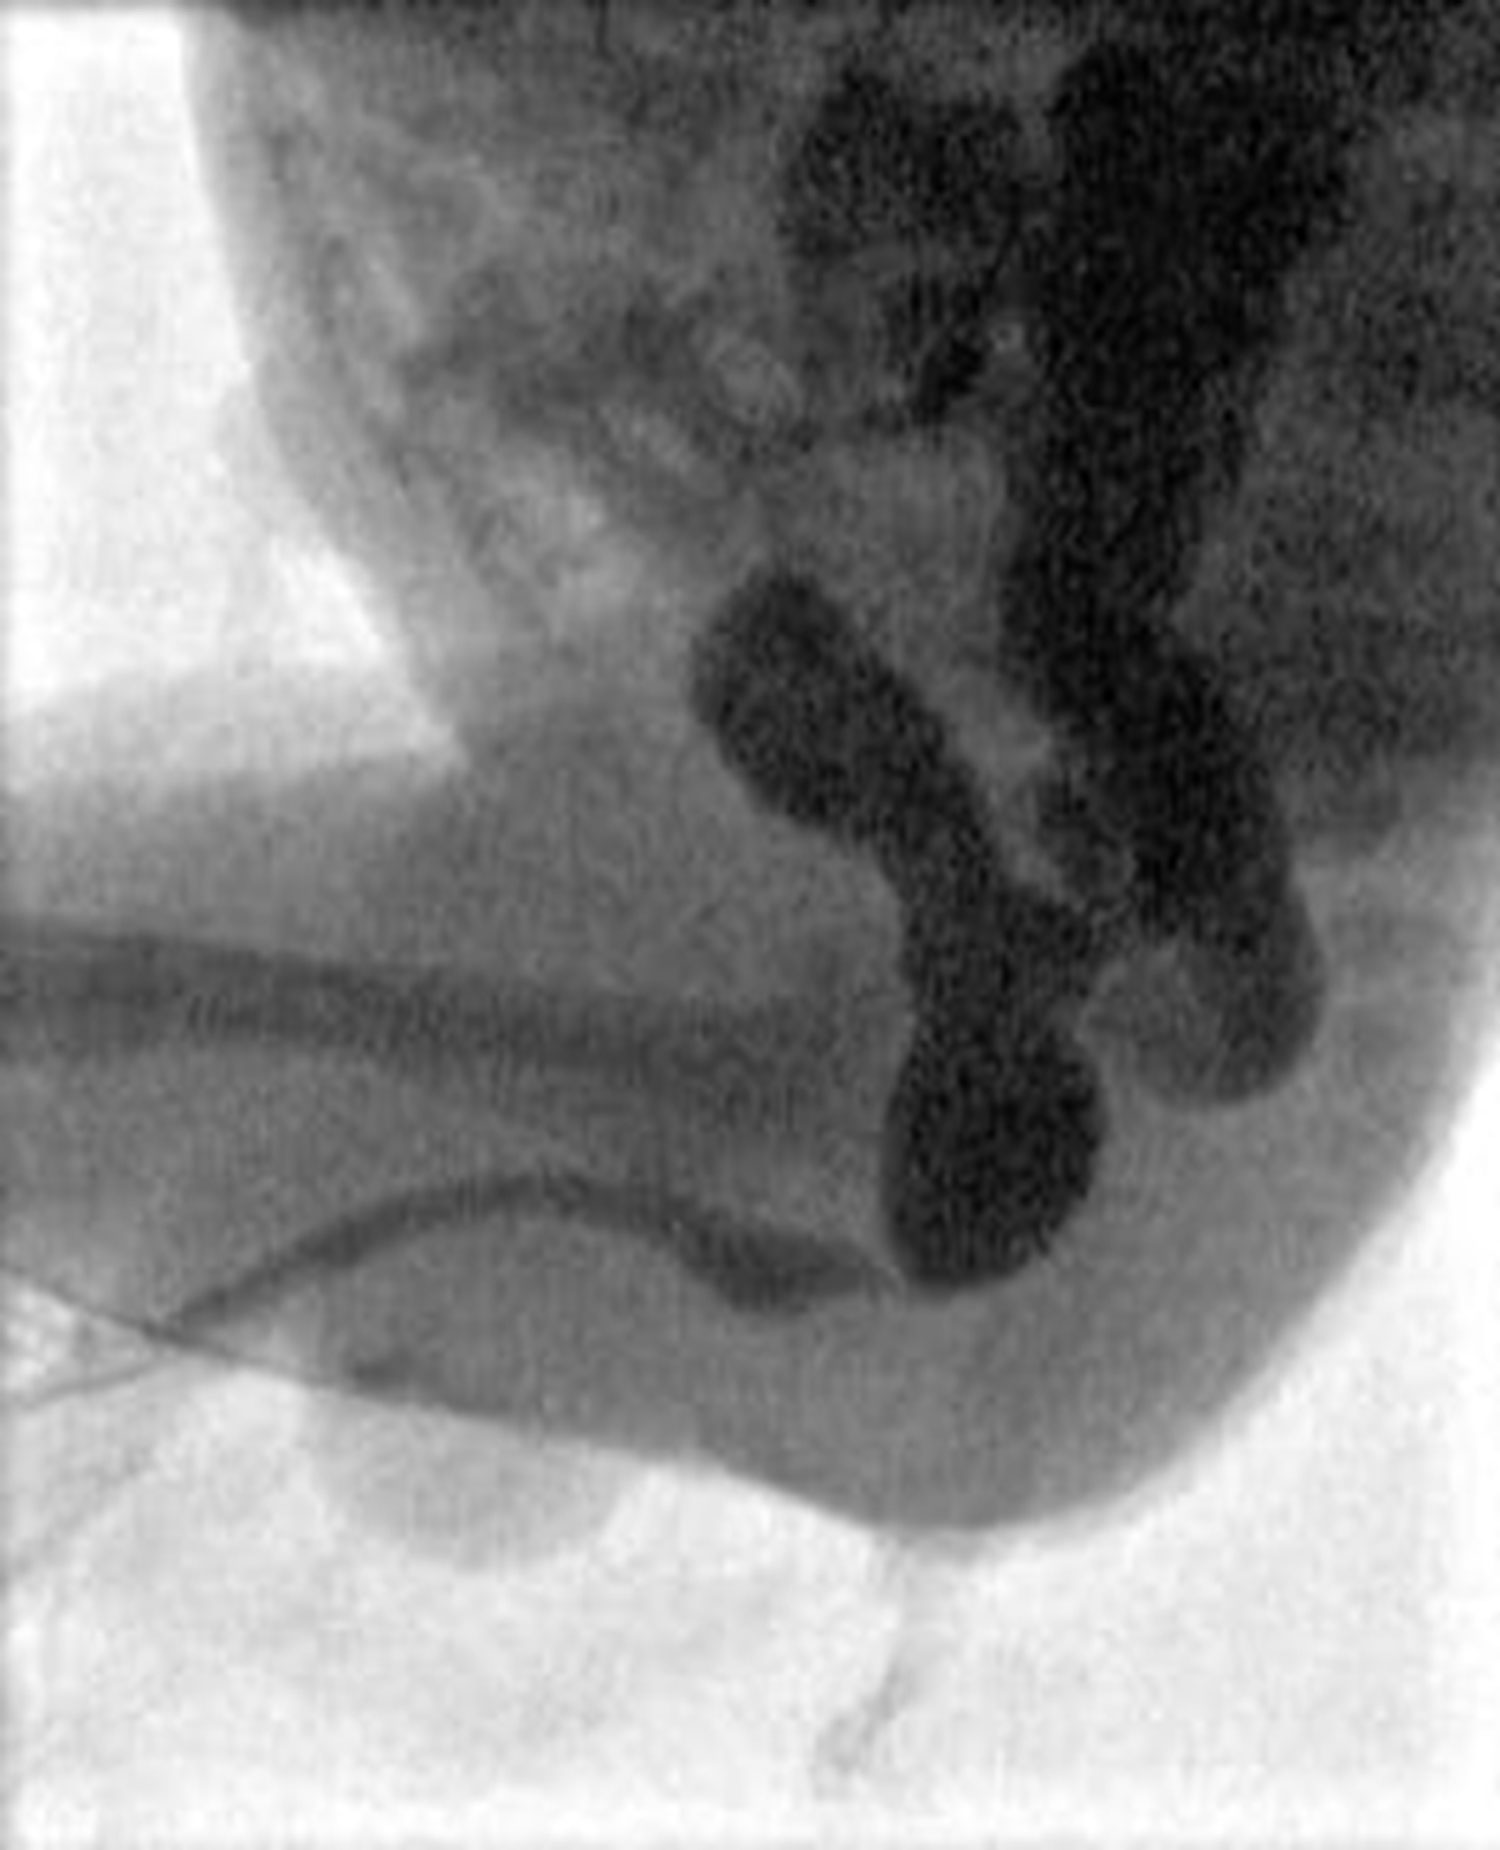

The index case is typically identified on antenatal ultrasound scan, or early postnatally. Ultrasound shows bilateral hydroureteronephrosis, distended and thick-walled bladder and dilated posterior urethra with the characteristic keyhole sign. These findings are generally confirmed by a micturating cystourethrogram (MCUG) performed after birth. Other possible signs on MCUG are bladder trabeculations, dilated posterior urethra, hypertrophied bladder neck (spinning top sign) with or without vesico-ureteric reflux (Figure 2). This index case represents the severest form of the disease, which most clinicians are familiar with. However, milder cases that present during late childhood, may not demonstrate all these cardinal signs [4].

Figure 2: Top: ultrasound scan images showing hydronephrosis, and key-hole sign.

Bottom: MCUG showing dilated posterior urethra with transition point at level of PUV, and high grade reflux.